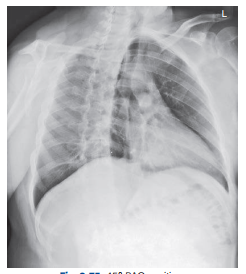

What chest position is this?

Lateral